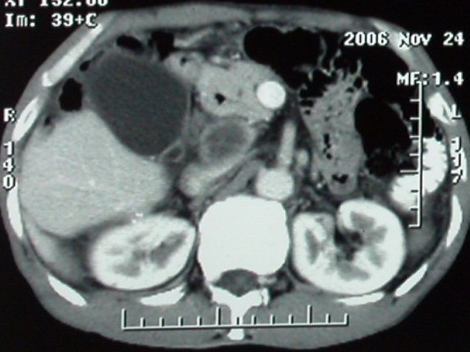

增强ct所见【动脉增强期】

门脉主干及肠系膜上静脉近端明显增粗,尤其前者呈等低混杂密度,增强后周围见轻度环形强化。明显占位效应。肝内外胆管见大量气体影。胆囊明显增大。

影像表现:胆囊扩张、肝内胆管不扩张,且见肝脏内树枝样气体影;十二指肠后方等密度占位,中心有不规则囊变区。增强实质部分轻度强化。下部腔静脉未强化------有栓子吗?

ct表现:1,胰腺钩突后方肿块,不均强化,中心密度低,钩突及门静脉前移。2:肝右后叶不均强化灶,突出肝表面,3:胆囊明显增大,肝内胆管及肝总管内积气。4:腹腔内少量积液。

胆囊扩张、肝内胆管不扩张,且见肝脏内气体影;十二指肠后方等密度占位,中心有不规则囊变区。增强实质部分强化。下部腔静脉未强化------有栓子吗?